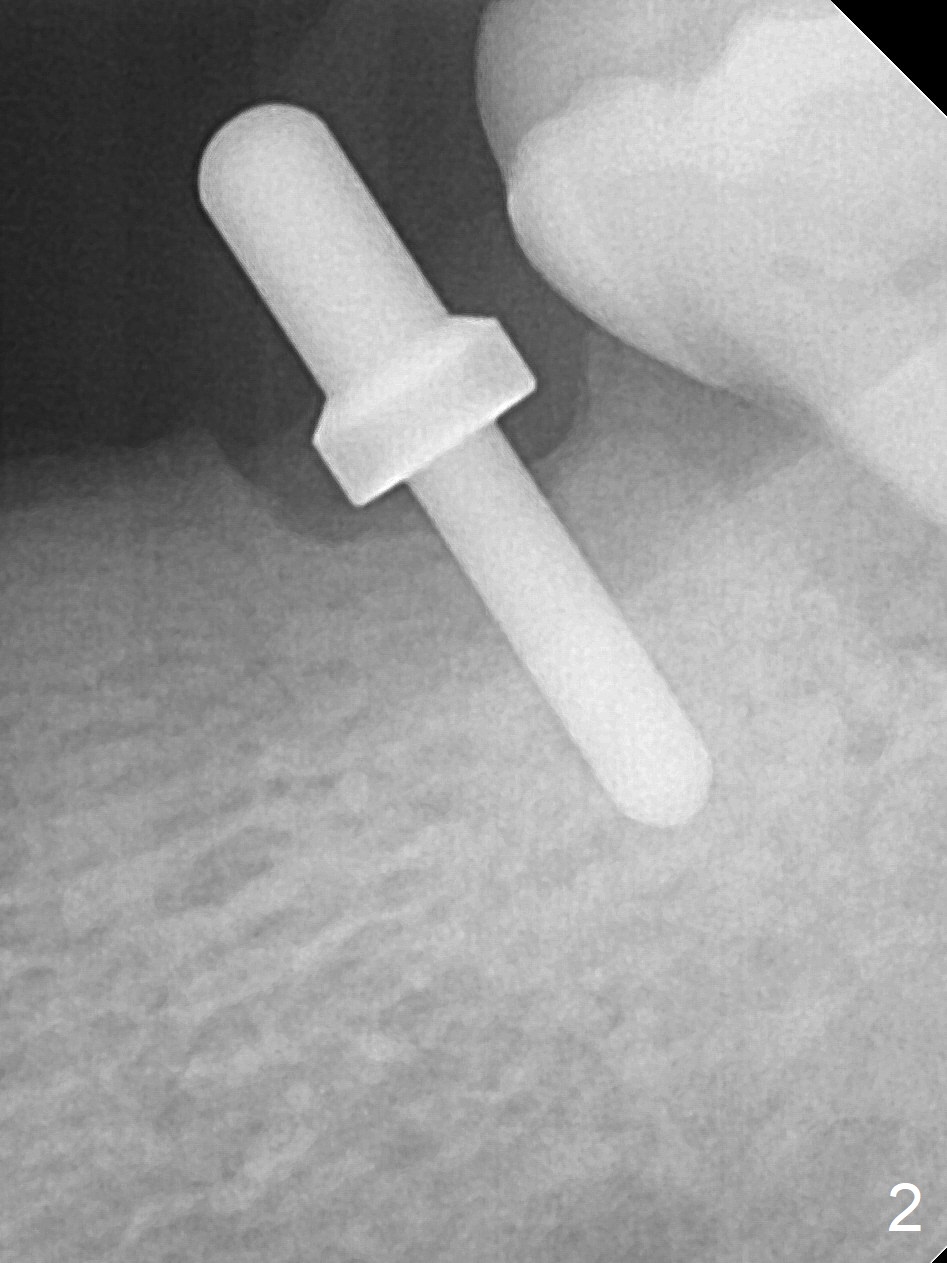

Preop photo confirms the lower left posterior pointed ridge (Fig.1). After ridge reduction and 2 mm drill for 8 mm, a parallel pin is inserted (Fig.2). A 3.8x8 mm SM implant is placed with >50 Ncm (Fig.3). The coronal threads (buccodistal) is covered with VeraGraft after placement of 4.1x5(3) mm healing abutment. The tooth #17 is not planned for extraction while the implant is osteointegrated. The tooth appears to be too loose and is extracted ~ 1.5 months postop. The implant seems to be osteointegrated 3 months postop (Fig.4). The healing abutment is changed to ball abutments with 4 mm (Fig.5) and 2 mm (Fig.6) cuffs. In fact the latter stays. What is the special device at the site of #18 (ring, Fig.7 <)?